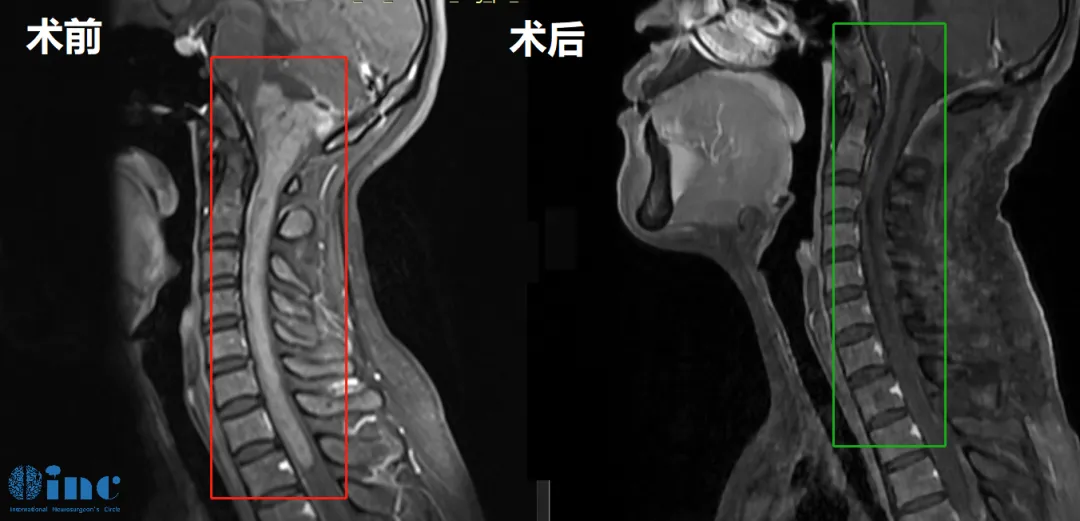

术前MR

看着影像片子上这条长度可怕的肿瘤,同为医务工作者的郑女士非常清楚手术的风险,脑干是生命中枢,脊髓是连接大脑与周围神经系统的主要通路,其中一处长肿瘤,不管肿瘤带来的威胁还是手术的风险,都是难以想象的,何况自己的这条病变范围累及15cm的大肿瘤。能安全手术的主刀医生也非常少,在查阅了许多专业的医学资料后,郑女士将目光锁定在国际脑干手术专家——INC德国巴特朗菲教授身上。看着年幼的孩子,和身边为自己担忧的爱人,郑女士决定寻求他的示范手术……

北京时间2022年11月23日,苏州大学附属第四医院手术室,历经12个半小时的高难度手术,终于从33岁郑女士的脑中,成功切除一颗巨大的脑干-脊髓髓内肿瘤!该肿瘤起源于脑干下部,累及延髓和颅颈交界区,且向下方延伸到整个颈部脊髓以及一直到第一胸椎水平,病变累及范围近15cm,这个位置的手术稍有不慎,患者可能就要面临瘫痪、呼吸心跳暂停、昏迷植物人等毁灭性的结果。为了更好的保护该名患者的正常神经功能并切除肿瘤,仅仅延髓、脊髓部位的肿瘤剥离就用了4个小时。